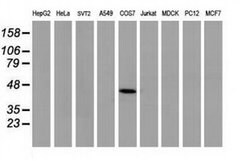

| Applications | Flow Cytometry, Immunocytochemistry, Immunofluorescence, Western Blot |